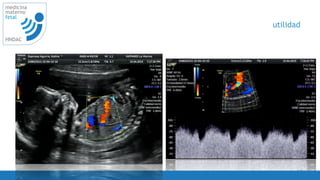

utilidad

• Diagnostico de insuficiencia placentaria

• RCIU

• Embarazo multiple